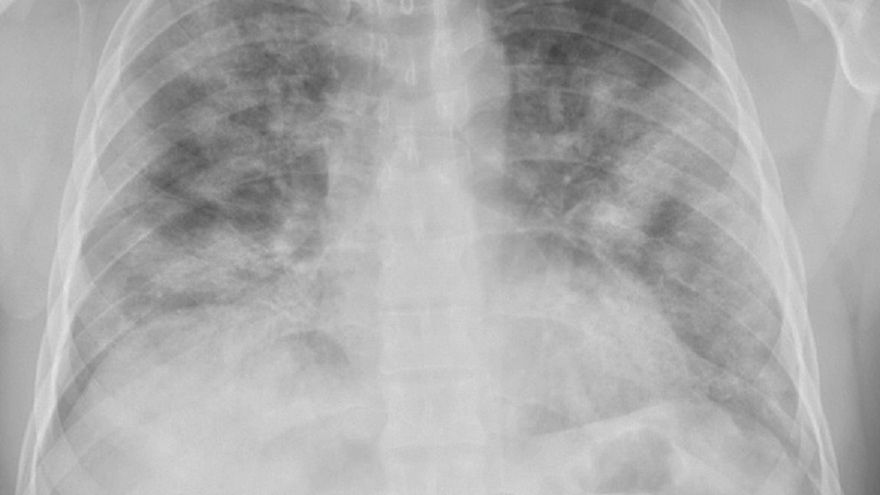

Okazuje się, że nawet osoby, które nie mają objawów zakażenia koronawirusem, mogą mieć poważne zmiany w płucach. Zmętnienie płuc to zjawisko, które może wystąpić u każdego chorego i jest dowodem na to, że COVID-19 jest niebezpieczny nawet przy łagodnym przebiegu.

płucaZmętnienie płuc występuje u wielu osób, które nie mają objawów.

Badacze ujawnili, że ponad 40 proc. ma zmętnienie płuc. Jest to zacienienia typu mlecznego szkła i możne je zobaczyć dopiero na skanach tomografu komputerowego. To oznacza, że nawet jeśli nie ma się typowych objawów, koronawirus wciąż działa na płuca.

Zmętnienie płuc było widoczne u pacjentów z różnym przebiegiem choroby. To jednoznaczny dowód, że wirus jest niebezpieczny w każdym przypadku i może pozostawić nieodwracalne zmiany.

Taki fragment płuca jest oznaką, że toczy się tam proces zapalny. Nie wiadomo, czy te zmiany w płucach samoistnie się zagoją po zwalczeniu infekcji, czy też pozostawią po sobie blizny - mówi Aileen Marty lekarz z Florida International University w Miami na Florydzie.

Nie wiadomo, jakie dokładnie konsekwencje może mieć zmętnienie płuc w przypadku zakażonych. Teorie potwierdza badanie z Japonii. 712 zakażonych przebywało na kwarantannie, a połowa z nich nie wykazywała żadnych objawów. Zmętnienie płuc pojawiło się u większości badanych.